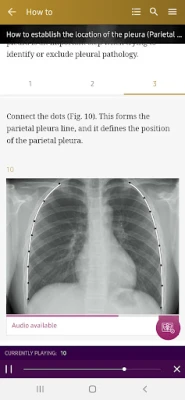

How To’s – 34 step-by-step guides, with annotated x-rays, to illustrate key skills needed to confidentially interpret chest x-ray.

Radiological Anatomy – Descriptions of various anatomical structures as they would appear on PA and lateral chest x-rays.